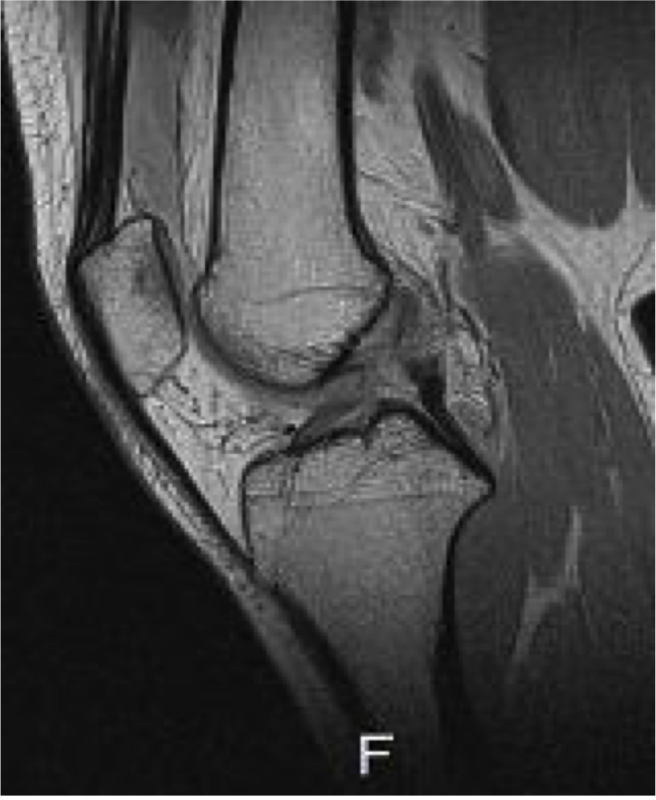

MRI

術前術後

ACLの連続性がなく、途絶している。再建靭帯の成熟を認める。